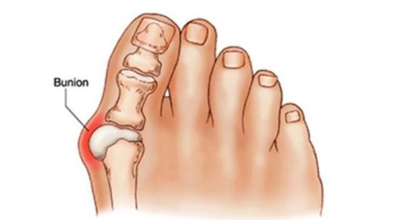

무지외반증 치료법

보존적 요법은 변형이 심하지 않은 경우 먼저 고려되는 치료법입니다. 굽이 높고 신발코가 뾰족한 신발을 피하고, 편한 신발을 착용해 발의 압박을 최소화시켜요. 신발 안에 중족골 패드나 발가락교정기 등 교정 도구를 착용해 압력을 재분배해서 증상을 완화시켜요. 그리고 보존적인 요법으로 증상이 완화되지 않거나 통증이 무척 심한 경우 수술이 고려되어요.

초기 단계에서는 건막류(두꺼운 혹)를 절제하는 건막류절제술을 시행해요. 돌출된 건막류를 절제해서 각을 교정하고 짧아진 근육 또는 연부조직을 늘려주는 비교적 간단한 수술입니다. 다른 발가락의 변형이 동반되거나 뼈의 과잉성장이 심하면 뼈를 깎고 방향을 돌린 뒤 발가락이 똑바로 펴지도록 철사로 고정시키는 등 교정절골술을 시행해요. 양 발이 모두 변형된 경우 대부분이 한 번에 한쪽만 수술해요.